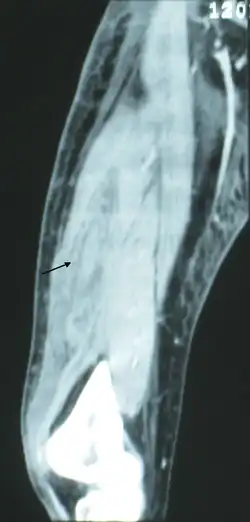

Plain radiography (X-ray)

It is difficult to distinguish NF from cellulitis in earlier stages of the disease using plain radiography.[15] X-rays can detect subcutaneous emphysema (gas in the subcutaneous tissue), which is strongly suggestive of necrotizing changes. However, air is often a late-stage finding, and not all necrotizing skin infections create subcutaneous emphysema. Hence, radiography is not recommended for the initial diagnosis of NF.[15] However, it may be able to identify the source of infection, such as foreign bodies or fractures, and thus aid in subsequent treatment.[15]